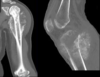

¿Qué se ve en la Rx de osteosarcoma?

- Destrucción ósea - Reacción perióstica: rayos de sol, piel de cebolla, triángulo de Codman - Masa de tejidos blandos

¿Qué signo es este?

Piel de cebolla --> osteosarcoma

113

Rayos de sol --> osteosarcoma